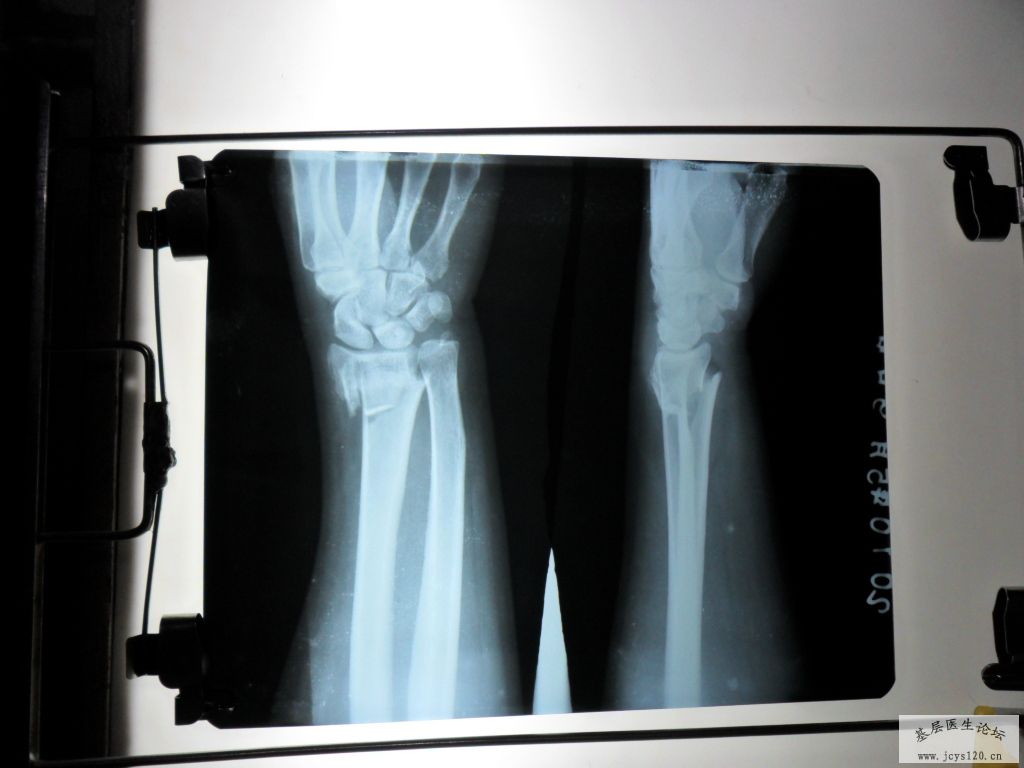

桡骨远端粉碎性骨折复位前后对比!一小时前急诊的病例!

一小时前,有一妇女因为去田间放水,不慎摔倒在田埂上,摔倒时因害怕伤着头,条件反射式的将右手撑在地上,右手剧烈疼痛,所以来诊,给予急诊X光摄片,呈右手远端粉碎性骨折,断端重叠移位,并有小块碎骨片嵌插在断端,片照好后,由我和助手握住右手骨折端两侧开始徐徐用力做拔伸牵引,我估计到重叠的断端分离后,将患者的手呈后前位,(掌心向上),再在骨折端施行了正骨八法中的某些手法,复位好后,敷上中药,夹板,再复查了一张X光片子,15分钟后,片子出来一看,复位一次成功,达到功能复位,随后开了3天的西药让病人回家去了,以下是该患者的片子: